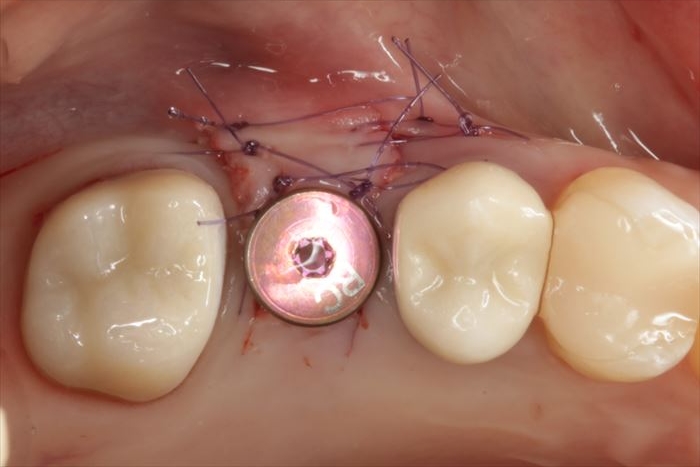

粘膜内部の骨膜に減張切開を加え伸展性を確保し、吸収性の縫合糸で縫合しました。

_

本日のインプラント埋入オペの終了です。